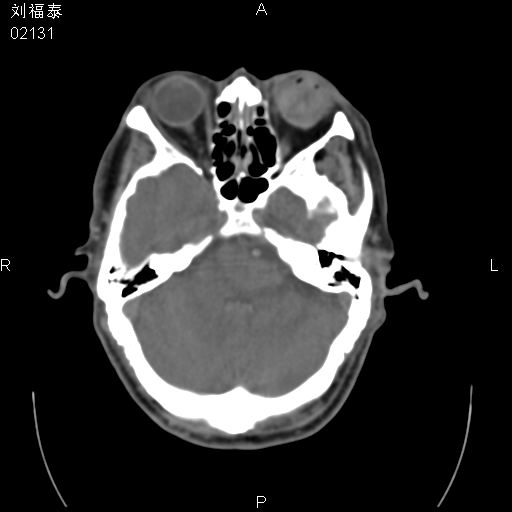

以下是引用余辉在2008-3-4 14:00:00的发言:[br]考虑左眼球黑色素瘤或血管源性肿瘤可能性大,建议增强检查

以下是引用余辉在2008-3-4 14:00:00的发言:[br]考虑眼球黑色素瘤或血管源性肿瘤可能性大,建议增强检查

以下是引用zsl6918在2008-3-4 15:08:00的发言:[br]现有征象只能提示球内出血,视网膜脱落,至于是否为肿瘤性病变需mri检查。